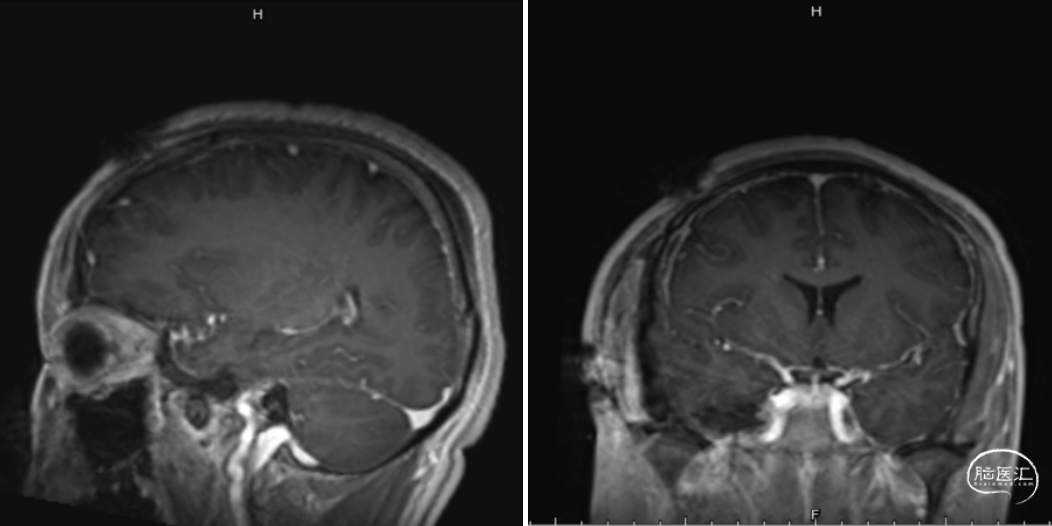

术后影像学

三叉神经鞘瘤常有明确包膜,对于中颅窝型三叉神经鞘瘤,其向内侧挤压海绵窦,但两者之间存在膜性边界,因此,单纯海绵窦神经鞘瘤可以理解为硬膜外病变,经硬膜外入路解剖清晰、操作简洁、脑损伤发生率低、能较好控制海绵窦出血(“第十期:扩大中颅窝入路经硬膜外切除三叉神经鞘瘤”我科已有相应病例汇报)。但本例肿瘤起源于三叉神经脑干端,从后颅窝生长至中颅窝(海绵窦旁),从圆孔向下生长至翼腭窝。中后颅窝肿瘤大部位于硬膜下,海绵窦侧壁、岩尖部位的肿瘤体积相对较小,故手术入路选择经硬膜下切除中后颅窝病变,可清晰辨认三叉神经主体及分支,且能够更加从容处理海绵窦侧壁肿瘤。而翼腭窝为硬膜外病变,故经硬膜外入路切除翼腭窝区域肿瘤。

本病例是个很有意思的病例:肿瘤从后颅窝至中颅窝再至翼腭窝,考验手术团队对该病例的解剖认识及手术入路的选择。但是,对于手术入路的选择并无绝对定式,需根据肿瘤具体位置、大小、形态、质地、走行与神经及血管的毗邻粘连关系、外科医师经验等,综合决策。